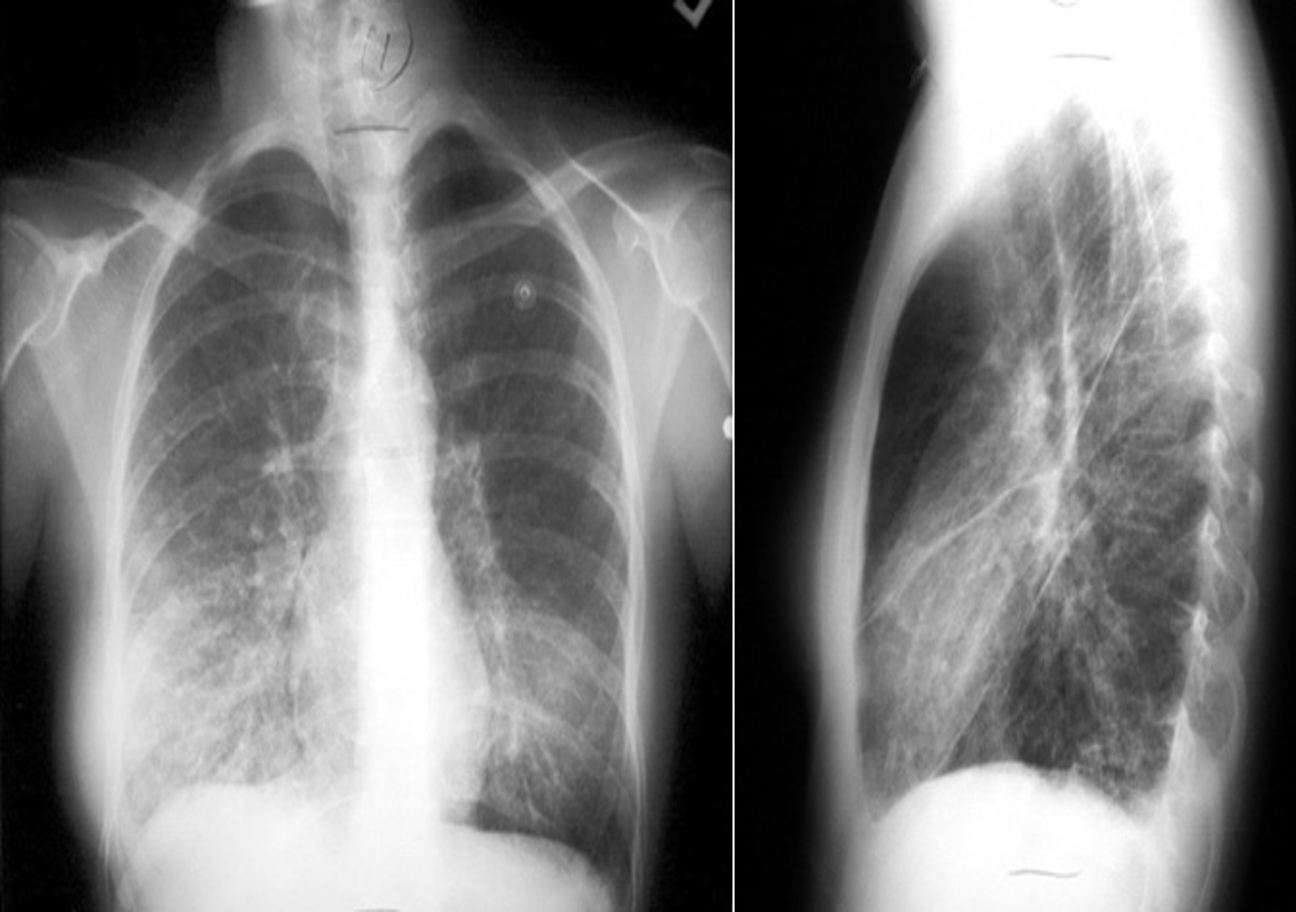

Image of chest x-ray displaying the interstitial pattern seen in viral pneumonia. The interstitial pattern shows fine lines radiating from the hila.

These chest X rays compare clear, healthy lungs with the cloudy, inflamed lung tissue of pneumonia.

Right lower lobe consolidation in a patient with bacterial pneumonia.

Anteroposterior radiograph from a child with a round pneumonia.

X-ray view of mycoplasma pneumonia

RT. lower lobe; Lobar pneumonia: Opacity of one or more pulmonary lobes & Presence of air bronchograms

- Right lower lobe is most commonly affected by pneumonia

- Spine blackness increased reversibly (Spine sign); lower part opaque

Bronchopneumonia:

- Poorly defined patchy infiltrates scattered throughout the lungs.

- Presence of air bronchograms